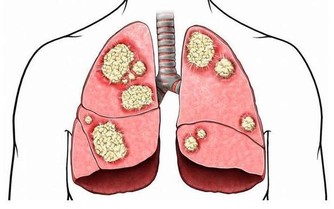

研究發現,霉變食物含有黃曲霉素,它是1類致癌物,只需1毫克的劑量,就可使人發生急性中毒。若是持續微量攝入,可導致生長障礙、肝臟慢性損傷、肝硬化等。

新鮮魚生味道鮮美,讓人欲罷不能。但常見的淡水魚生、醉蝦、醉蟹、醉螺、鯉魚、草魚、大頭魚等都是肝吸蟲的宿主,人如果生吃這些食物,很可能感染肝吸蟲,出現膽管炎、肝硬化等症,嚴重者可導致肝癌。